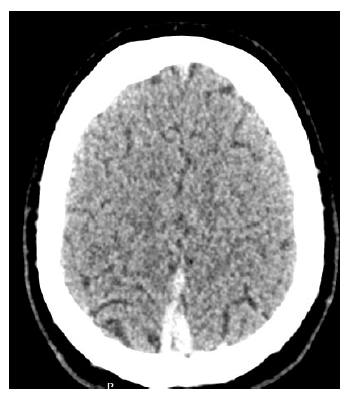

Uma paciente de 30 anos de idade, puérpera, obesa, procura atendimento hospitalar em razão de cefaleia occipital de severa intensidade iniciada há dois dias. Previamente hígida, nega atopias e episódios prévios. Ao exame: Glasgow 15, pupilas isofotorreagentes, sem déficits focais, sem sinais de irritação meningorradicular, frequência cardíaca: 120 bpm, frequência respiratória: 18 ipm e SaO2: 99% em ar ambiente. A paciente realizou tomografia computadorizada sem contraste.

Com base nesse caso clínico e na imagem da tomografia apresentada, julgue os itens a seguir.